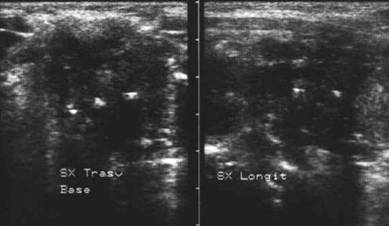

Loja laterocervicala dreapta.

Loja laterocervicala stanga

Femeie 31 ani. Leziuni hipoecogene, neomogene laterocervical bilateral. Tiroidectomie totala pentru neoplasm papilar cu extensie extracapsulara si metastaze linfonodale (T4 N1 M0) in urma cu 2 ani. Terapia radiometabolica.

Examen citologic: celule epiteliale gigante ca in granulomul

de corp strain; fibroza cronica granulomatoasa supurativa. Tireoglobulina din lichidul

de lavaj: nedozabil.

Aceeasi pacienta – fara semnal de vascularizatie

interna.